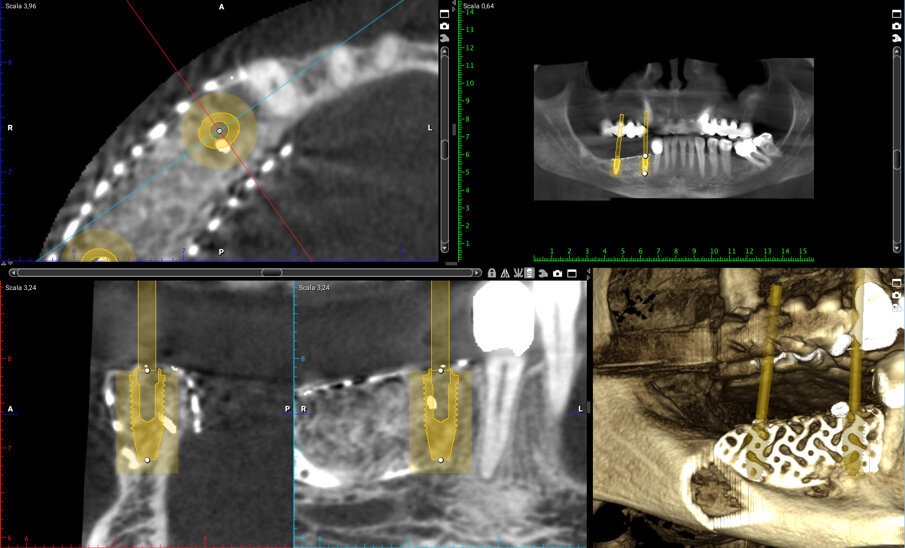

I file Dicom ottenuti sono stati inviati all’azienda produttrice delle griglie e da questi sono stati ricava - ti modelli tridimensionali in resina che riproducessero in modo fedele il deficit osseo; su questi modelli è stata costruita virtualmente e digitalmente la griglia che, dopo approvazione del clinico, è stata prodotta e inviata ai clinici (Figg. 2a, 2b). Le dimensioni mesio-distali della griglia erano di 21 mm e l’entità volumetri ca del deficit osseo di 1,24 cm 3 . Il piano di trattamento ha previsto, nel marzo 2018, un primo intervento di ricostruzione ossea del difetto mediante una griglia customizzata in titanio e, dopo 7 mesi (ottobre 2018), un secondo intervento ha permesso la rimozione della griglia con contestuale inserimento di 2 impianti endossei in posizione 4.4 e 4.6 per supportare un ponte fisso di 3 elementi protesici.

La paziente è stata dimessa con la seguente terapia domiciliare: una dieta fredda e liquida per le prime 24 ore e una dieta tiepida e morbida fino alla rimozione dei punti di sutura, oltre alla continuazione della terapia antibiotica, antisettica e antiedemigena associata alla terapia antidolorifica con ketoprofene e sale di lisina, bustina da 80 mg, al bisogno. Subito dopo l’intervento è stata eseguita una CBCT di controllo per verificare l’incremento ottenuto (Figg. 6a, 6b). Le suture sono state rimosse 20 giorni dopo l’intervento e la paziente è stata sottoposta a controlli clinici a 1-3-6 mesi dall’intervento che non hanno evidenziato alcuna complicanza. Al sesto mese, è stata eseguita una nuova CBCT (Fig. 7), utilizzando la medesima dima diagnostica usata in fase pre-operatoria, che ha mostrato la corretta integrazione del materiale innestato (Fig. 8) e, a 7 mesi dall’intervento, si è proceduto alla rimozione della griglia e all’inserimento di due impianti “root form” e “bone level” nella zona rigenerata. Un lembo in cresta a tutto spessore, simile a quello eseguito nella prima fase chirurgica, ha permesso l’accesso alla griglia e la stessa dima utilizzata per la diagnosi è stata adattata creando fori di circa 4 mm di diametro per ottimizzare il posizionamento degli impianti (Fig. 9).

Fig. 7_Sezione di CBCT a distanza di 6 mesi dall’intervento ricostruttivo che mostra il notevole incremento osseo e la pianificazione pre-implantare.

L’incremento osseo medio in altezza e spessore, valutato con un software dedicato (Planmeca Romexis Viewer®) immediatamente dopo e a 6 mesi dalla ricostruzione con una CBCT, considerando come riferimenti i margini interni della griglia (margini esterni dell’innesto) e quelli del difetto osseo da correggere (osso basale), è stato – rispettivamente – di 8.09 mm e 8.02 mm. A distanza di 6 mesi la media di riassorbimento osseo verticale e orizzontale è stata rispettivamente di 0.35 mm e 0.4 mm con una percentuale media del 4% verticale e del 5% orizzontale.